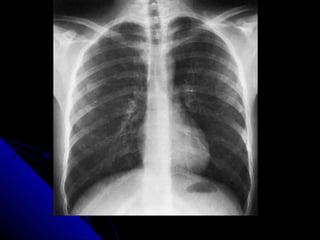

OOrriieennttaattiioonn

TThhee uussuuaall iinnddiiccaattiioonn ffoorr AAPP iiss aa ppaattiieenntt

wwhhoo iiss ccoonnffiinneedd ttoo bbeedd.. IIff iinn ddoouubbtt,, llooookk aatt

tthhee rreellaattiioonnsshhiipp ooff tthhee ssccaappuullaaee ttoo tthhee lluunngg

mmaarrggiinnss.. AA PPAA vviieeww sshhoowwss tthhee ssccaappuullaaee

cclleeaarr ooff tthhee lluunnggss wwhhiillsstt iinn AAPP pprroojjeeccttiioonn

tthheeyy aallmmoosstt aallwwaayyss oovveerrllaapp.. TThhee ccaarrddiiaacc

sshhaaddooww llooookkss bbiiggggeerr oonn aann AAPP vviieeww..

PA AP

16 OOrriieennttaattiioonn TThheeuussuuaall iinnddiiccaattiioonn ffoorr AAPP iiss aa ppaattiieenntt wwhhoo iiss ccoonnffiinneedd ttoo bbeedd.. IIff iinn ddoouubbtt,, llooookk aatt tthhee rreellaattiioonnsshhiipp ooff tthhee ssccaappuullaaee ttoo tthhee lluunngg mmaarrggiinnss.. AA PPAA vviieeww sshhoowwss tthhee ssccaappuullaaee cclleeaarr ooff tthhee lluunnggss wwhhiillsstt iinn AAPP pprroojjeeccttiioonn tthheeyy aallmmoosstt aallwwaayyss oovveerrllaapp.. TThhee ccaarrddiiaacc sshhaaddooww llooookkss bbiiggggeerr oonn aann AAPP vviieeww..